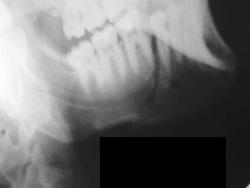

А это визави.

Зашинировали

У этого 3 г. назад нелеченная травма, теперь остеомиелит